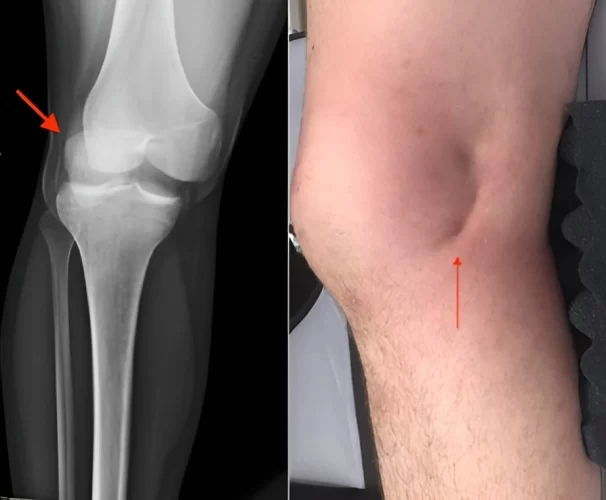

در حالت طبیعی، کشکک با هدایت رباطها و عضلات اطراف آن، در مسیر مشخصی حرکت میکند اما اگر در اثر ضربه مستقیم، پیچش ناگهانی زانو یا ضعف ساختاری، از شیار اصلی خود خارج شود، به آن دررفتگی کشکک زانو (Patellar Dislocation) گفته میشود. همانطور که در عکس دررفتگی کشکک زانو مشخص است، کشکک زانو جا به جا شده است و برای درمان، پزشک باید آن را جا بیندازد و به جای اصلی برگرداند.